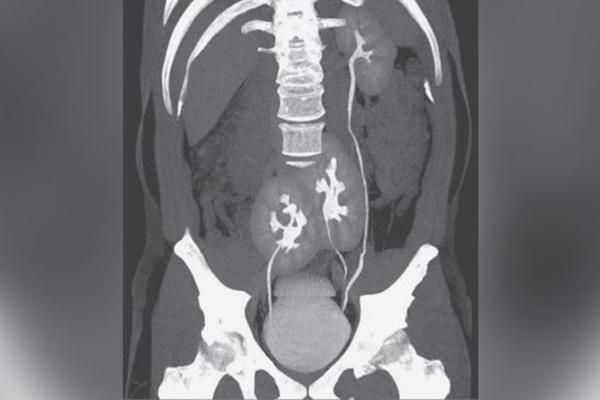

Hình ảnh chụp CT cho thấy ba quả thận của người đàn ông: Một quả thận xuất hiện bình thường ở bên trái và hai quả thận hợp nhất ở xương chậu. (Ảnh: © Tạp chí Y học New England © 2020)

Tuy nhiên, đây không phải là điều duy nhất khiến các bác sĩ quan tâm. Họ còn phát hiện ra một điều rằng người đàn ông này có một đặc điểm giải phẫu khác thường. Anh ta có tới 3 quả thận chứ không phải 2 quả thận như người bình thường. Theo báo cáo cho biết, một quả thận trông bình thường ở bên trái và hai quả thận hợp nhất nằm gần xương chậu.

Thông thường, mỗi quả thận được kết nối với bàng quang thông qua một ống duy nhất gọi là niệu quản. Trong trường hợp của người đàn ông này, một trong những quả thận gần xương chậu được kết nối trực tiếp với bàng quang thông qua niệu quản. Tuy nhiên, niệu quản của quả thận gần xương chậu còn lại nối với niệu quản của thận bình thường ở bên trái trước khi nó đi vào bàng quang.